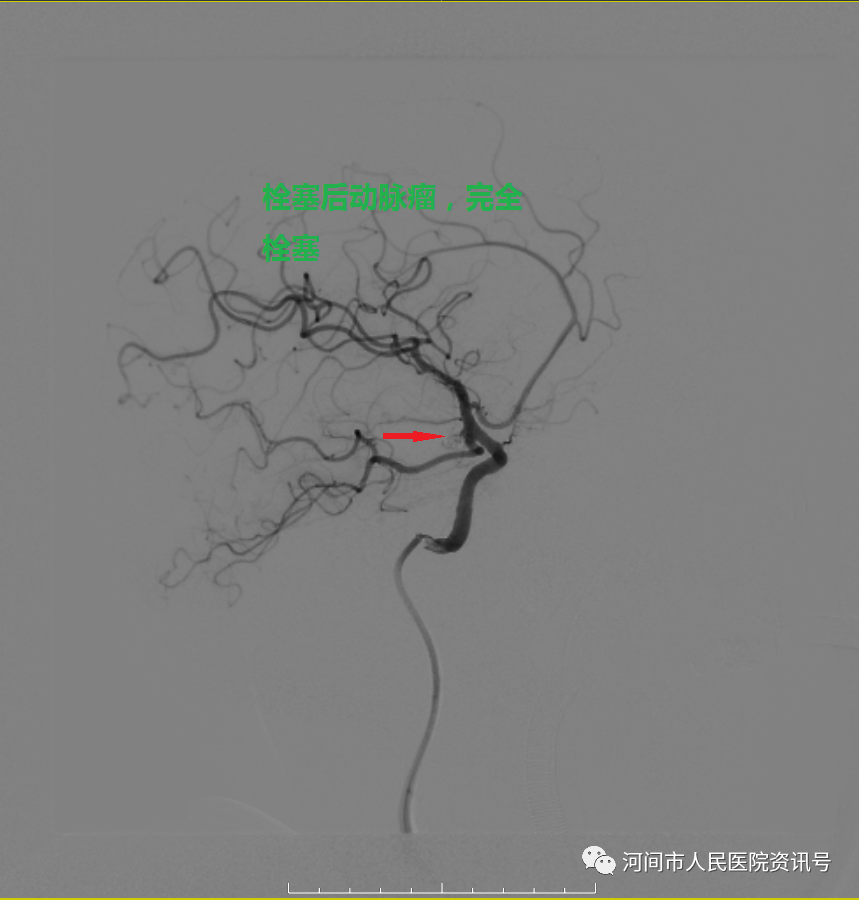

急诊立即开通绿色通道收入神经内三科。神经内三科吴俐欣主任紧急完善头颈CTA,报告显示右侧颈内动脉C7段动脉瘤,长径约5.5mm,同时头颅CT示患者颅内出血较前明显增加。患者突然意识不清、处于昏迷状态,继而呼吸骤停。紧急情况下,立即给予患者气管插管,随后转入重症监护室继续治疗。经神经内三科、ICU、神经外科等多科通力协作,于4月2日15时20分,神经内三科副主任杜文辉、医师刘建伟在介入科、麻醉科配合下,为患者成功施行了“全脑血管造影术+颅内动脉瘤栓塞术”,神经外科医师对患者进行了脑室外引流术,及时挽救了患者生命。在医护团队的精心照料下,目前,患者意识清醒,言语流利,四肢活动自如。

栓塞术后